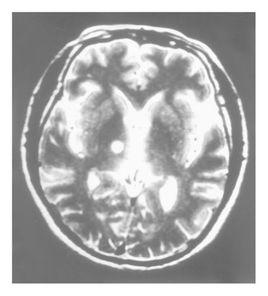

除傳統方法外,近年來還可採用MRI定位導向手術。由於高解析度MRI和薄層掃描的套用,能清晰顯示AC、PC和基底節區腦深部結構的圖像,為靶點的直接準確定位提供了條件。此種方法無造影痛苦,也比CT解析度高,如有專用軟體配合,直接在顯示器上進行靶點定位和計算靶點坐標,則更加省時和準確。